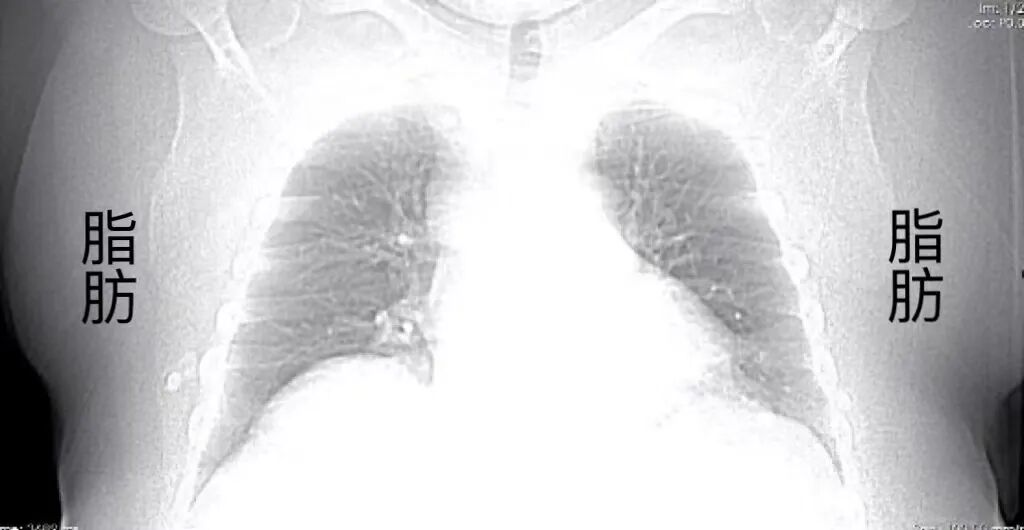

ge ct有哪些型号不怕超重 自由呼吸 | GE Revolution CT显神奇,实现完美冠脉CTA检查!_https://www.jmylbn.com_新闻资讯_第6张

血管显示清晰,没有搏动伪影

ge ct有哪些型号不怕超重 自由呼吸 | GE Revolution CT显神奇,实现完美冠脉CTA检查!_https://www.jmylbn.com_新闻资讯_第7张

ge ct有哪些型号不怕超重 自由呼吸 | GE Revolution CT显神奇,实现完美冠脉CTA检查!_https://www.jmylbn.com_新闻资讯_第8张

ge ct有哪些型号不怕超重 自由呼吸 | GE Revolution CT显神奇,实现完美冠脉CTA检查!_https://www.jmylbn.com_新闻资讯_第9张

ge ct有哪些型号不怕超重 自由呼吸 | GE Revolution CT显神奇,实现完美冠脉CTA检查!_https://www.jmylbn.com_新闻资讯_第10张

回旋支近端软斑块并管腔轻度狭窄